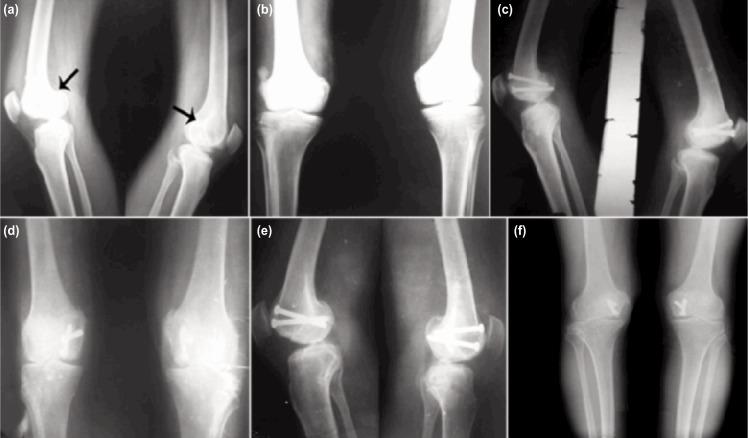

Isolated Hoffa fracture is an infrequent injury and little research has been done on this subject. The purpose of this study was to evaluate the functional outcome and complications of surgically managed Hoffa fractures with cannulated cancellous screw. Between 2011 and 2014, eight isolated Hoffa fractures in seven adult patients with mean age 39.8±11.9 years (range 25-60 years) were managed with cannulated cancellous screw of 6.5mm diameter applied in anterior to posterior direction using swashbuckler and medial parapatellar approach for lateral and medial Hoffa fractures respectively. All patients were evaluated using knee evaluation score after two years or longer. Mean follow up was 28±3.8 months (range 24-36 months). All fractures in the eight patients healed clinicoradiologically by the 16th week with excellent result in 87.5% cases and good in 12.5% cases. By the end of union, the range of motion (ROM) of the knee was 0° to 110° except in two patients. One patient had ROM 10°-100° and other had 15°-90°. Mean knee evaluation score was 87.5±10.4. There was no incidence of non-union, infection or avascular changes in the patients or loss of reduction till final follow up. Open reduction and fixation with two 6.5 mm cannulated cancellous screws with early mobilization yielded good functional outcome in isolated Hoffa fractures.

孤立性Hoffa骨折是一种罕见的损伤,对此主题的研究较少。本研究的目的是评估采用空心松质骨螺钉手术治疗Hoffa骨折的功能结果和并发症。2011年至2014年期间,对7例成年患者(平均年龄39.8±11.9岁,范围25 - 60岁)的8例孤立性Hoffa骨折进行了治疗,分别采用“海盗”入路和内侧髌旁入路,对外侧和内侧Hoffa骨折从前向后方向应用直径6.5mm的空心松质骨螺钉。所有患者在两年或更长时间后使用膝关节评估评分进行评估。平均随访时间为28±3.8个月(范围24 - 36个月)。8例患者的所有骨折在第16周时临床影像学愈合,87.5%的病例结果优秀,12.5%的病例结果良好。到骨折愈合结束时,除2例患者外,膝关节的活动范围(ROM)为0°至110°。1例患者的ROM为10° - 100°,另1例为15° - 90°。平均膝关节评估评分为87.5±10.4。直至最终随访,患者未发生骨不连、感染或缺血性改变,也没有复位丢失的情况。采用两枚6.5mm空心松质骨螺钉切开复位内固定并早期活动,在孤立性Hoffa骨折中取得了良好的功能结果。